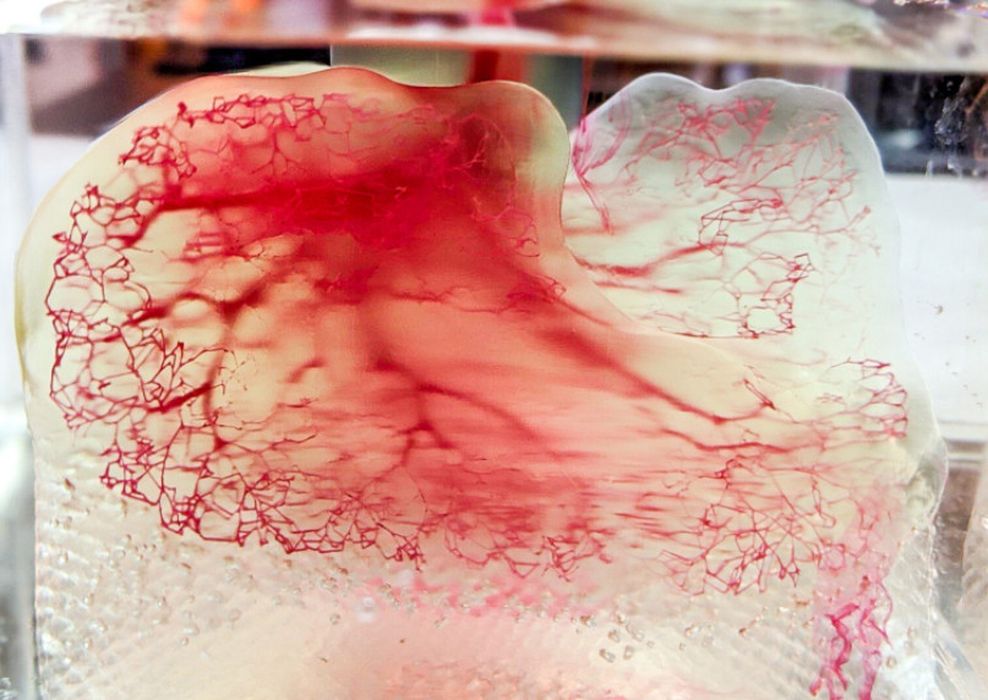

Readily3D Attempts Volumetric Human Organ Bioprinting

Readily3D, one of the first companies to tackle the new volumetric 3D printing process, has adapted their process for bioprinting.

TU/e Uses Xolography to 3D Print Living Cells

The research could lay the foundation for printing complex biological tissues, such as kidneys and muscles.